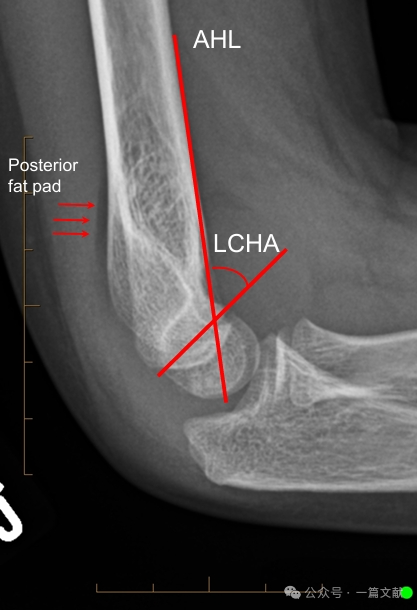

Alignment on Lateral Radiograph:

* Anterior Humeral Line (AHL): Should pass through the ossification center of the capitellum.

* Capitellar Anterior Angle: 30-40 degrees.

* Lateral Capitellohumeral Angle (LCHA): Should be less than 69 degrees.

* Posterior Fat Pad Sign: Highly suggestive of fracture (whereas an anterior fat pad sign can be seen without fracture).